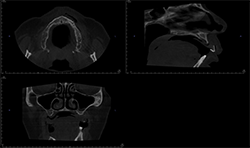

Case 4: 59-year-old woman with pain and sinus tract associated with endodontically treated #14

Periapical radiographs (Figs. 8A, 8B) show that radiolucent area around the mesial root of #14 and missing lamina dura. The apical lesion is close to the floor of the left maxillary sinus.

CBCT (Figs. 9A, 9B) reveals the lesion extends from the buccal cortex to the palatal cortex with furcation involvement and involves the palatal root. Mucosal thickening is noted along the floor of the left maxillary sinus, suggesting odontogenic origin. Tooth extraction would be recommended.